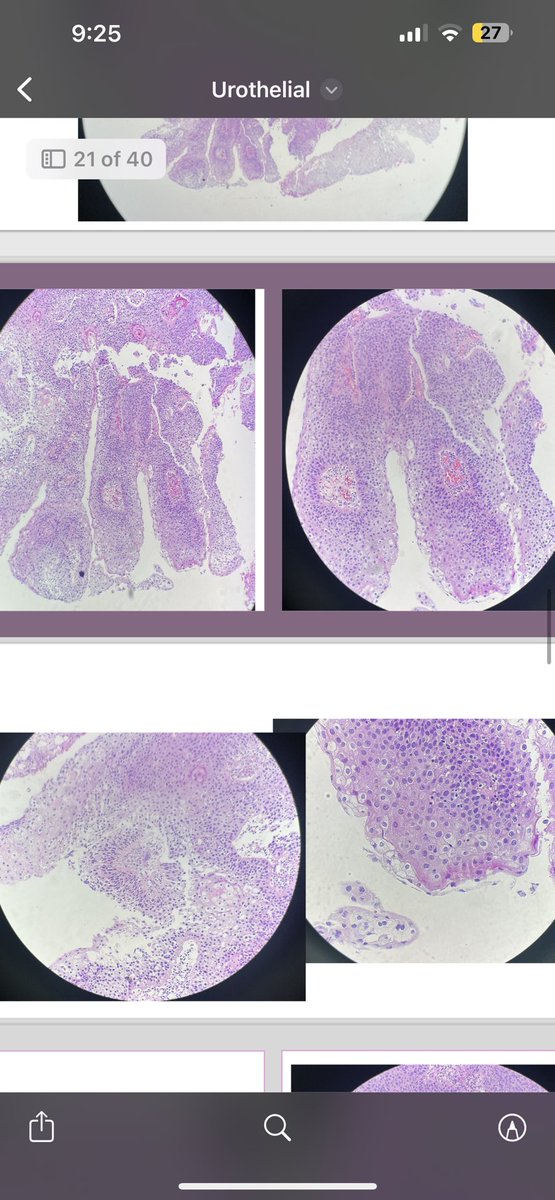

Paris category for urothelial carcinoma #MedTwitter #TwitterPath #GUPath

amnabruno's tweet image. Paris category for urothelial carcinoma

#MedTwitter #TwitterPath #GUPath